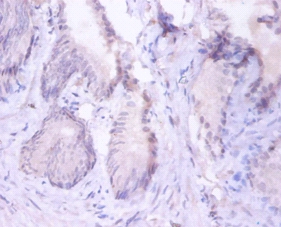

Immunohistochemical analysis of paraffin-embeded human colorectal carcinoma using #42251 at dilution of 1:100.

Immunohistochemical analysis of paraffin-embeded human prostate using #42251 at dilution of 1:100.